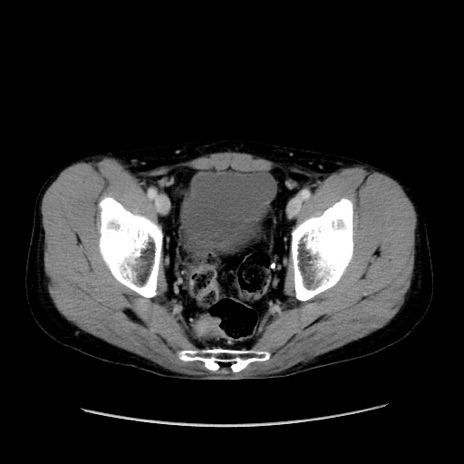

症例37(横断像)

【症例】40歳代 男性

【主訴】腹痛

【現病歴】4時間ほど前に電車に乗車中に臍部上より腹痛出現。徐々に増悪し起立困難となり、救急外来受診。生ものは数日食べていない。今朝お雑煮を食べた。

【身体所見】BT 36.8℃、BP 117/84mmHg、HR 91/min、SpO2 97%、苦悶様、腹部:臍上部広範囲圧痛あり、反跳痛±

【データ】WBC 8100、CRP 0.03